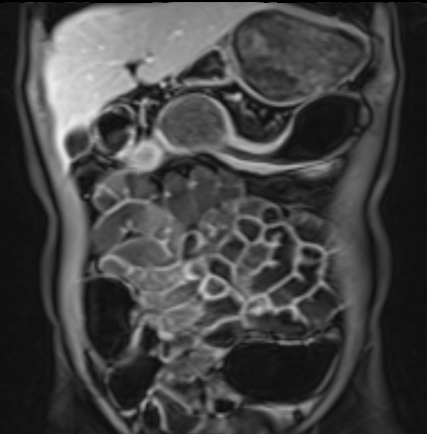

Ruột non đang viêm với dày thành và tín hiệu T2W thành ruột nhẹ (mũi tên) trên hình ảnh T2 axial có fat-sat. Có thể thấy giãn trước hẹp ở phía trên đoạn ruột bệnh lý.

Cường độ tín hiệu T2W thành ruột có thể được phân độ như sau khi sử dụng chuỗi xung T2 có fat-sat:

- Không tăng

thành ruột bình thường - Tăng nhẹ

thành ruột có màu xám đậm - Tăng vừa

thành ruột có màu xám nhạt - Tăng nhiều

thành ruột chứa các vùng tín hiệu cao màu trắng, gần bằng tín hiệu của nội dung lòng ruột.